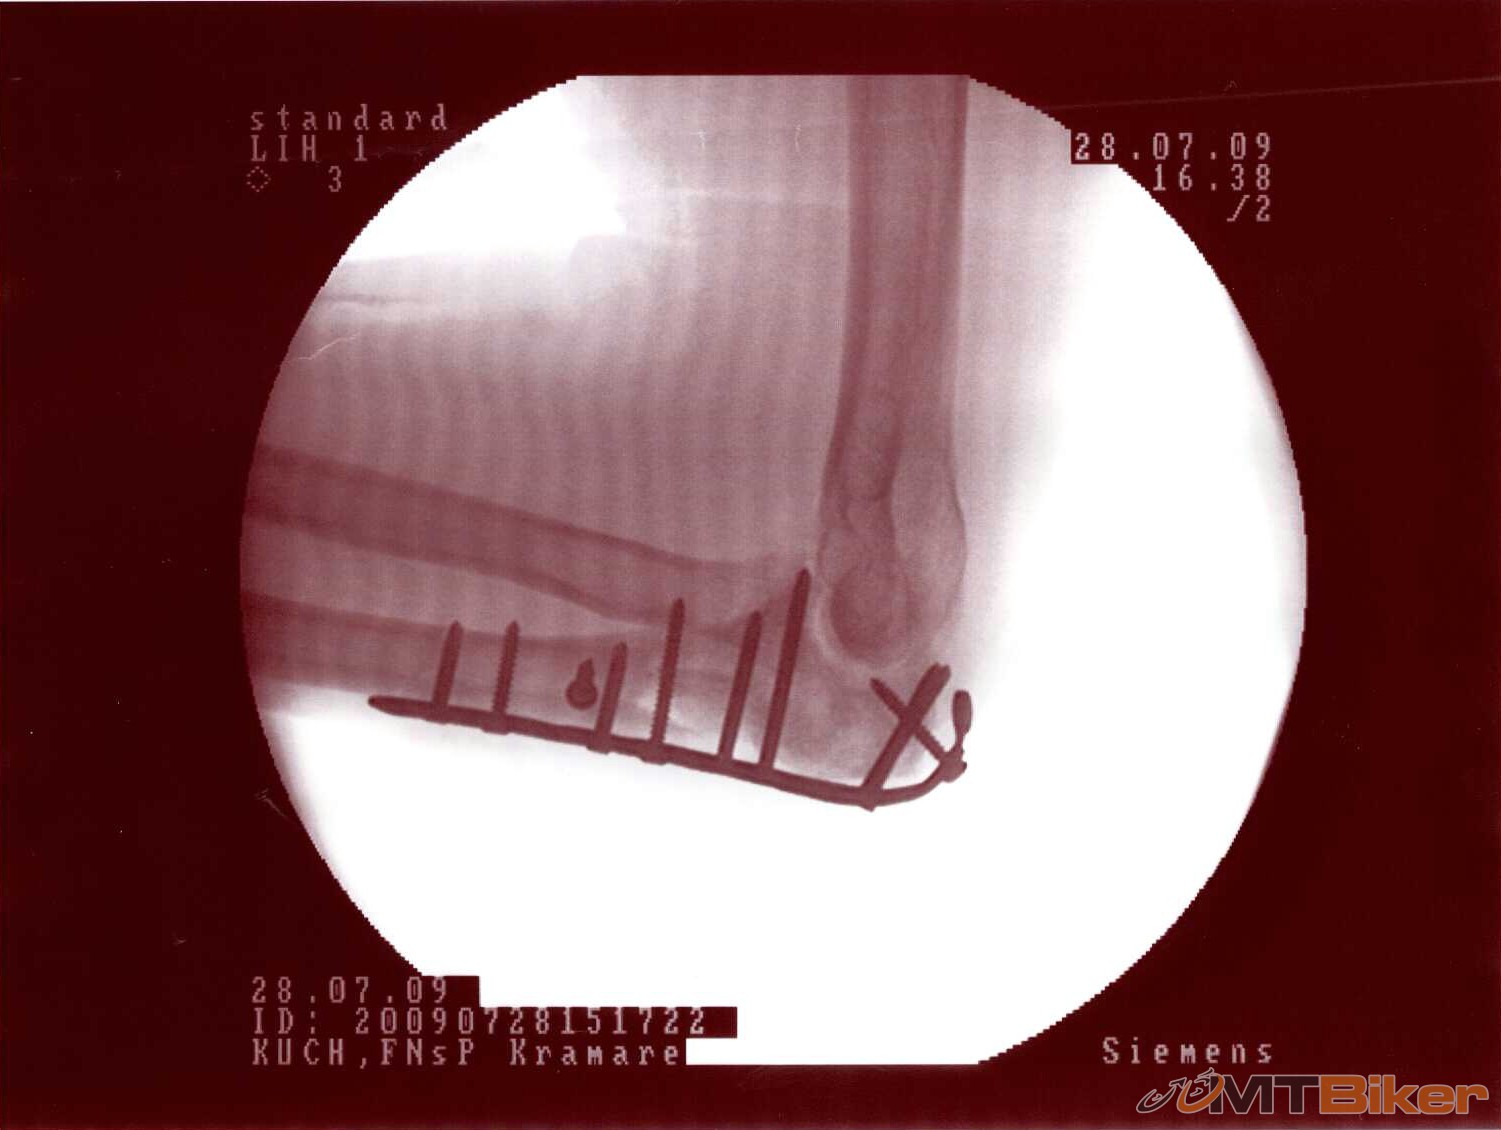

Pridám aj ja zo svojho. Stalo sa pred dvoma rokmi v júli, keby aspoň niekde v teréne ale prd! ráno pri ceste do práce. Čakal som na priechode pod Novým mostom v BA na zelenú, keď naskočila postavil som sa do pedálov a naplno zabral - raz, dva a na tretíkrát preskočila reťaz a ja som hodil ukážkového tigra cez riadidlá. Smola bola, že som si to nasmeroval ľavým lakťom priamo na obrubník takže ten si odniesol celých 90 kg mojej skromnej hmotnosti. Keby som padol na hlavu nič by sa nestalo ale na prilbe nebol ani šrabanček, rovnako nikde na tele nič ani ranka, akurát na stehne zozadu modrina ako dve dlane - od sedla. Takže všetko si odniesol ľavý lakeť. Výsledok vidíte: otvorená trieštivá zlomenina ľavého lakťa, krvi tam po mne zostalo ako po zabíjačke, odvoz RZP na Kramáre, 4 hodiny skladanie na operačke - titanová dlaha a 10 skrutiek. Odvtedy som na bike-u nesedel. Ako som už inde písal zanechalo to bohužiaľ trvalé následky, tá ruka už nefunguje tak ako by mala ale k bike-u ma to znovu ťahá, trochu rekreácie by som si rád doprial. Tak si to vychutnajte

Ja som prave s predlaktim a laktovym klbom doma za spolocnosti drotov a srobu. Mna zrazilo auto na bajku (presiel do protismeru a tam si ma nasiel).

tie drôty vyzerajú fakt sexi držím prsty nech sa to dá do pôvodného stavu

tie drôty vyzerajú fakt sexi